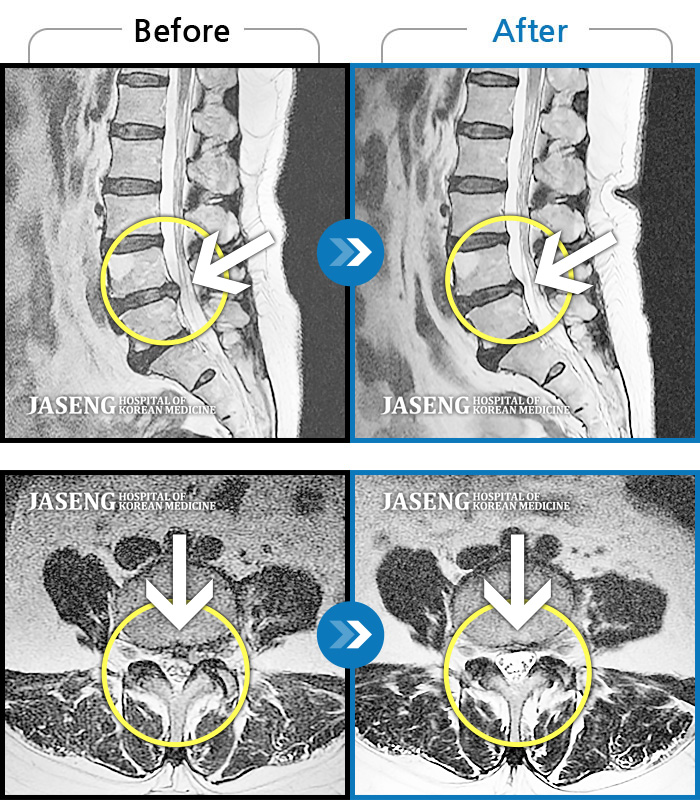

ȯںп Ǹ ǿ ԿǾ, ο ġ ۿ Ƿ ġḦ Ͻñ ٶϴ.